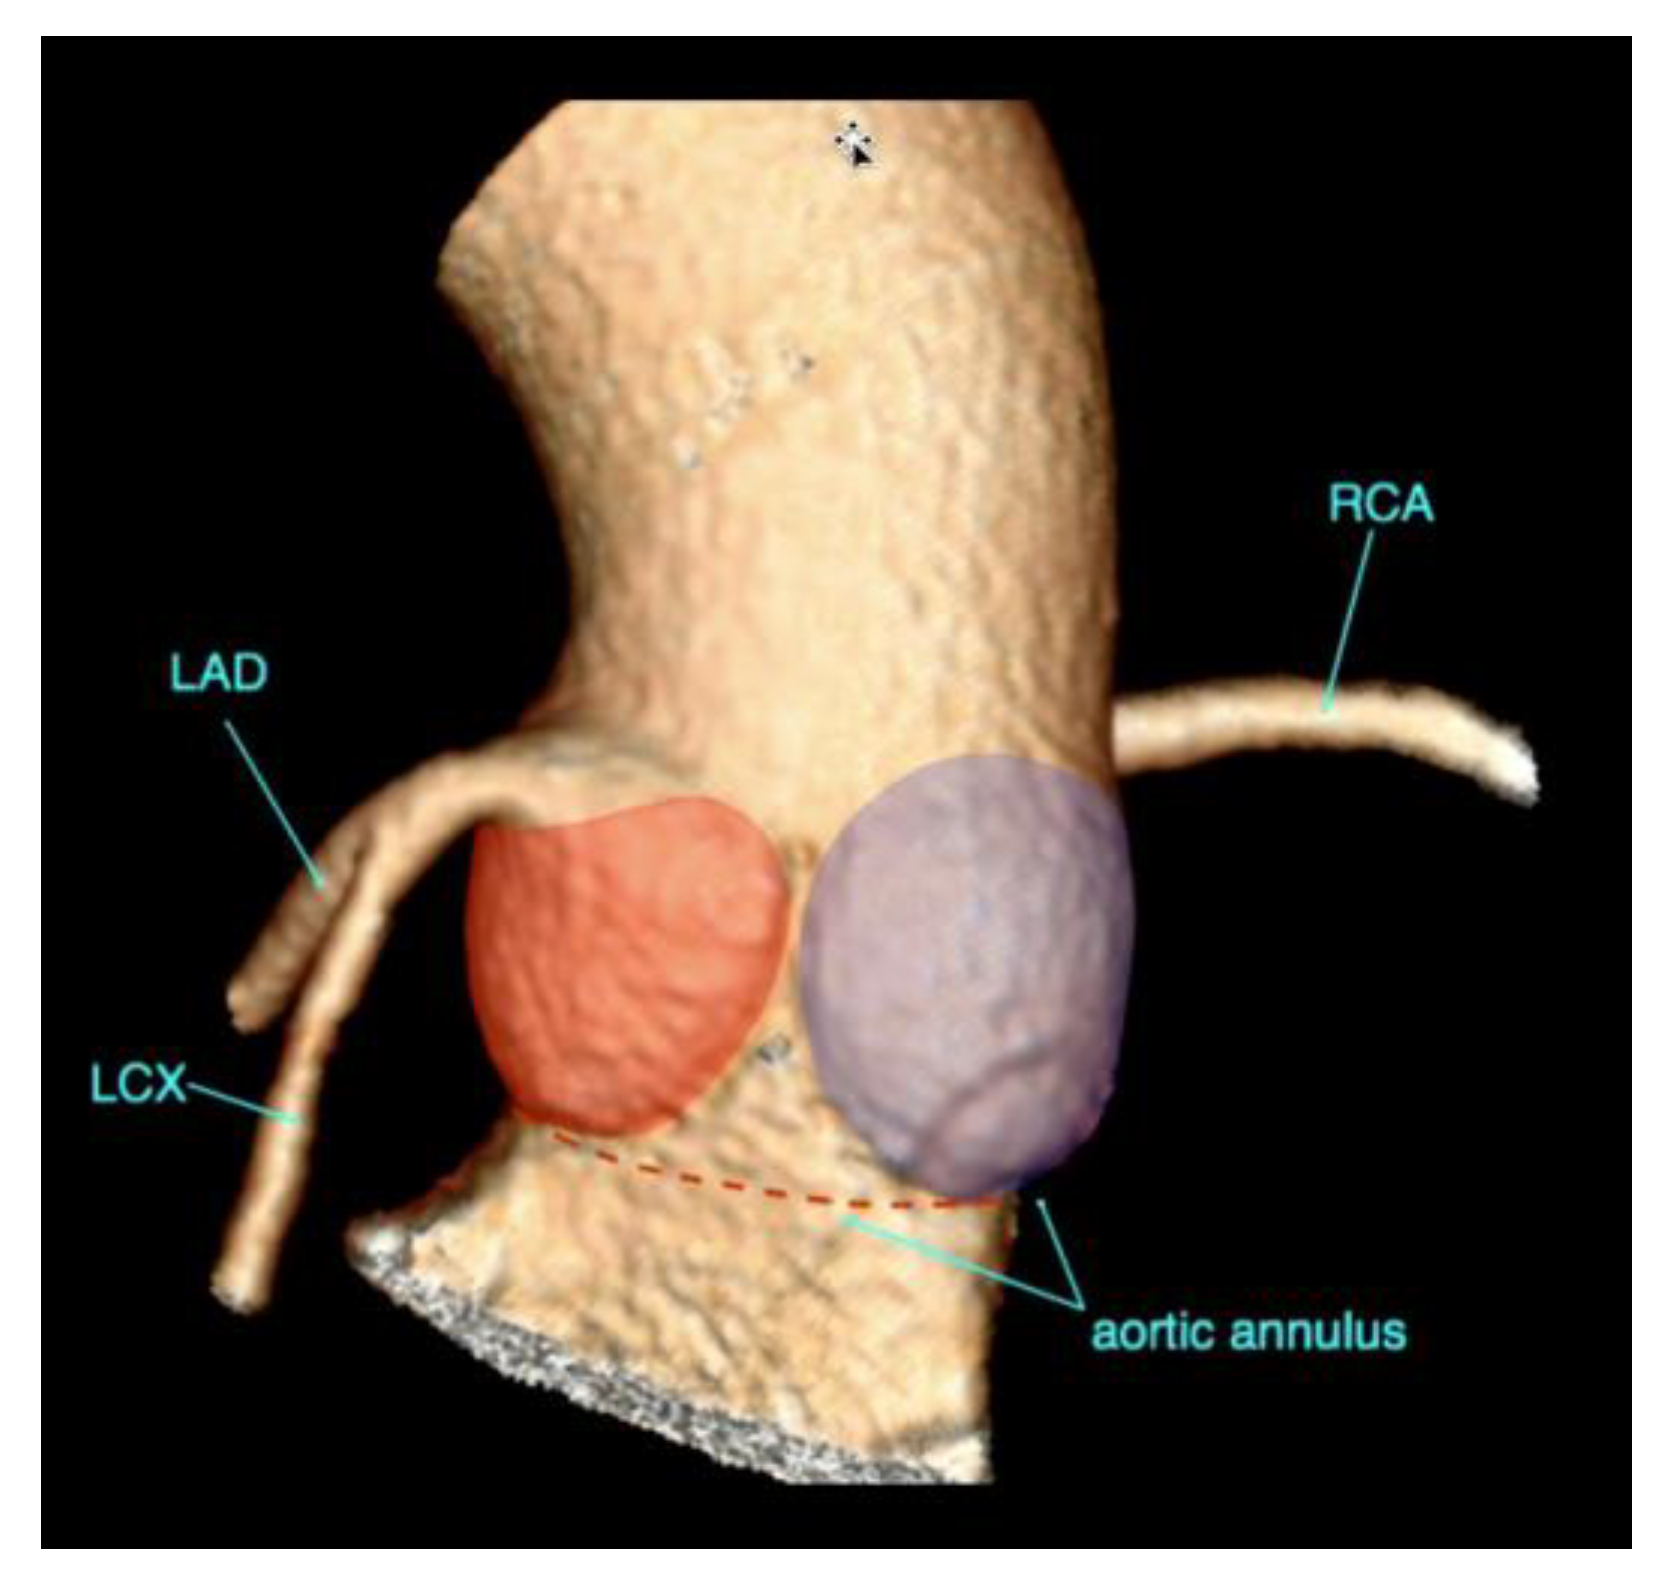

3. Transcatheter Aortic Valve Replacement

| Coronary ostia heights | Distance from annular plane to bottom of left and right coronary ostia | As a rule of thumb, a minimum diameter of 10 mm is considered the threshold to avid ostial coronary obstruction by migrated leaflet calcifications. |

| Sinus of Valsalva dimensions | Long- and short-axis cross-sectional diameters Largest cross-sectional diameter Commissure-to-cusp diameter Height of the coronary sinus | The aortic sinus needs to be wide enough to accommodate displaced native leaflet calcifications during the deployment of the THV. |

- Blanke, P.; Weir-McCall, J.R.; Achenbach, S.; Delgado, V.; Hausleiter, J.; Jilaihawi, H.; Marwan, M.; Nørgaard, B.L.; Piazza, N.; Schoenhagen, P.; et al. Computed tomography imaging in the context of transcatheter aortic valve implantation (TAVI)/transcatheter aortic valve replacement (TAVR): An expert consensus document of the Society of Cardiovascular Computed Tomography. JACC Cardiovasc. Imaging 2019, 13, 1–20. [Google Scholar] [CrossRef]